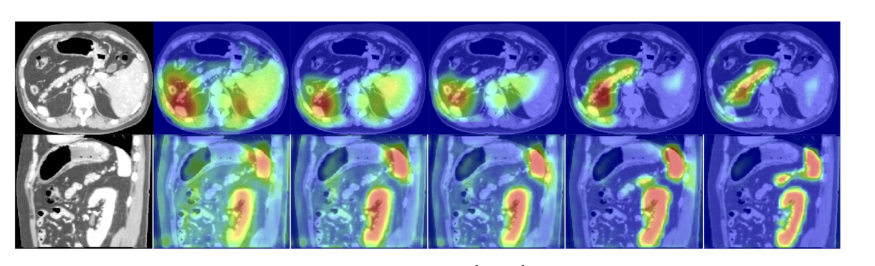

图中的xl为图1的绿色箭头,将深层次的语义特征输入门中进行特征筛选,g为图1中跳跃连接连接的部分

The filtered feature activations (d-e, i-j) are collected from multiple AGs, where a subset of organs is selected by each gate.